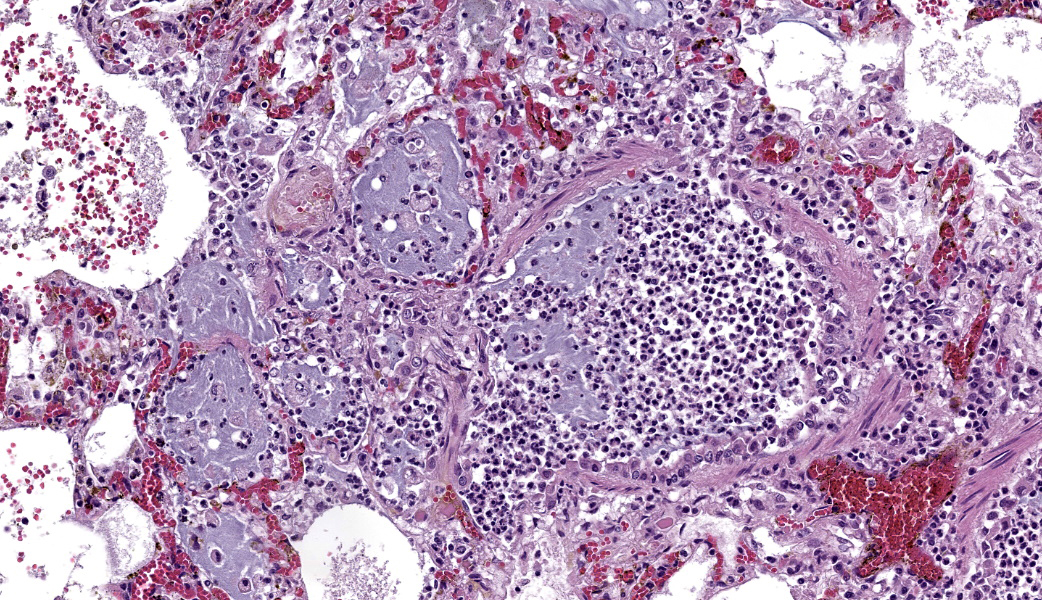

Typical pathological changes in equids with viral pneumonia include pulmonary consolidation in a lobular pattern separated by unaffected or overinflated lung lobules, or less commonly, a diffuse pattern of pneumonia.1 EIV infections complicated by secondary bacterial infections are characterized by fibrinosuppurative exudate and pulmonary consolidation, mostly restricted to the cranioventral pulmonary lobes (bronchopneumonia).1,12,13 Histopathologically, acute stages typically reveal rhinitis and tracheitis with epithelial necrosis and infiltrates of lymphocytes in the lamina propria. Subacute to chronic lesions consist of epithelial hyperplasia and squamous metaplasia.6,11 Affected lungs exhibit bronchointerstitial pneumonia with hyaline membranes in the alveoli, type II pneumocyte hyperplasia, and necrotizing bronchitis/bronchiolitis. Secondary bacterial bronchopneumonia may also develop.4,6,12

Lung: Pneumonia, bronchointerstitial, necrotizing and fibrinosuppurative, acute, multifocal to coalescing, marked, with thrombosis, edema, and hyaline membranes.

Determining differentials in a case of viral pneumonia in any species requires a working knowledge of viral pathogenesis and target cells to refine the list of potential offenders. In this case, the most striking hallmarks for influenza virus include the end-airway epithelial necrosis and patchy areas of hemorrhage. Influenza is both endotheliotropic and epitheliotropic and, while it affects epithelial cells in the upper airways, it has unique tropism for the type I and type II pneumocytes of the alveoli as well. It causes significant destruction to end-airways as a result. This key difference can help separate an influenza infection from other pneumotropic viruses, such as calicivirus in cats. (Feline calicivirus infection of the lung can look nearly identical to an H5N1 influenza virus infection in a cat, but the state of the end airways can help clue in the pathologist to which virus is most likely and can assist in decision-making for next testing steps. The more virulent strains of feline calicivirus can cause severe interstitial pneumonia, but they do not cause necrosis of end airways the way that influenza does.)